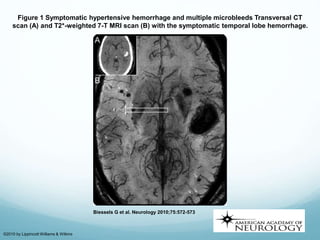

Figure 1 Symptomatic hypertensive hemorrhage and multiple microbleeds Transversal CT

scan (A) and T2*-weighted 7-T MRI scan (B) with the symptomatic temporal lobe hemorrhage.

Biessels G et al. Neurology 2010;75:572-573

©2010 by Lippincott Williams & Wilkins

Figure 1 Symptomatichypertensive hemorrhage and multiple microbleeds Transversal CT scan (A) and T2*-weighted 7-T MRI scan (B) with the symptomatic temporal lobe hemorrhage. Biessels G et al. Neurology 2010;75:572-573 ©2010 by Lippincott Williams & Wilkins